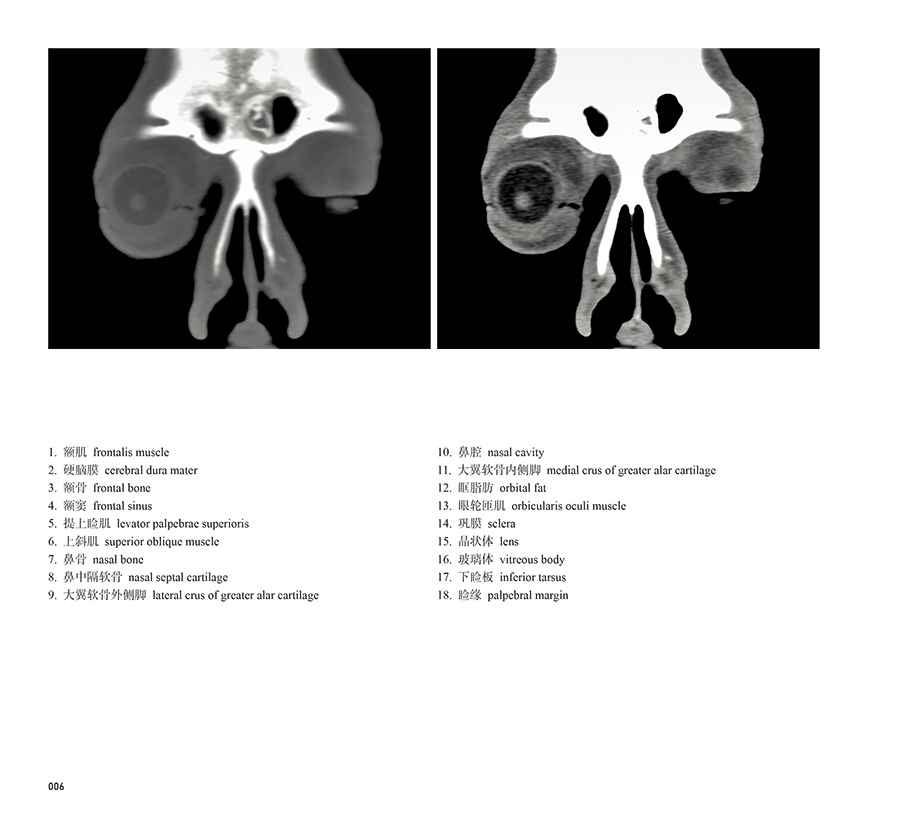

本书从数据集每隔1.2mm选取一幅图像,截取眼、耳、鼻及毗邻颅底的局部区域图像,共112幅图像。同时配以相应部位的CT图像对照。本书特色是断层解剖图利用数字图像处理技术优势,放大并清晰展示眼、耳、鼻及毗邻颅底断面的局部区域结构,组织色泽真实,甚至能够清晰显示肌肉纹理、筋膜纹路等细节结构,图像质量高于美国《人体断层解剖学彩色图谱》(引进版)类似图谱图像质量。对眼科、耳鼻咽喉科和神经内外科医生理解相关解剖结构有较大帮助。